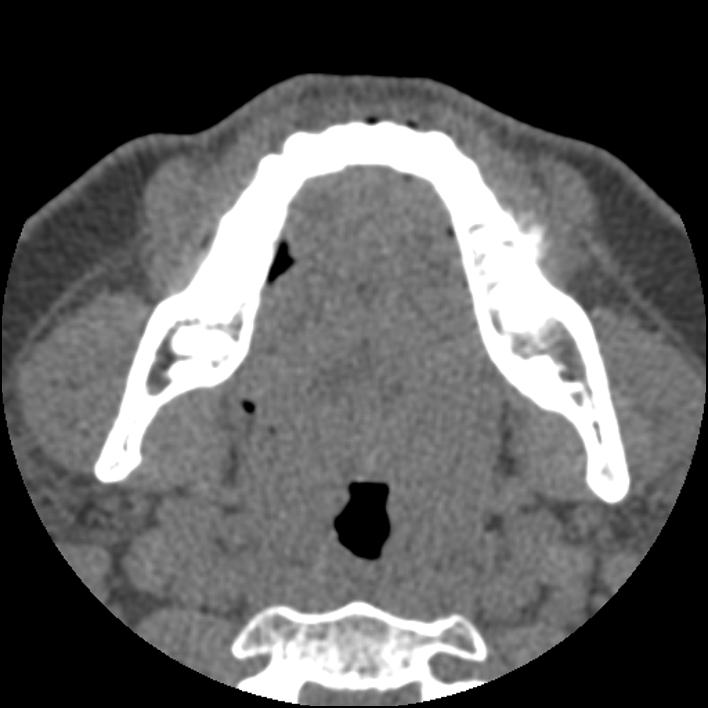

Figure 2 for case Chondroblastic osteosarcoma of the mandible

Figure 2